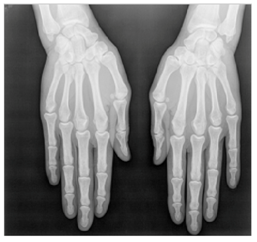

In this section, we present and analyze the results obtained with the proposed method, and compare it to methods proposed in similar works. The proposed watermarking system is implemented using MATLAB and executed on a Windows machine with the following characteristics: Intel R Core i5 processor, 4 GHz, 4 GB RAM, and Microsoft Windows 8 Professional operating system platform. In our experiments, we have used DICOM images of size 512 × 512 pixels as shown in Table 1.

Table 1.

Original images.